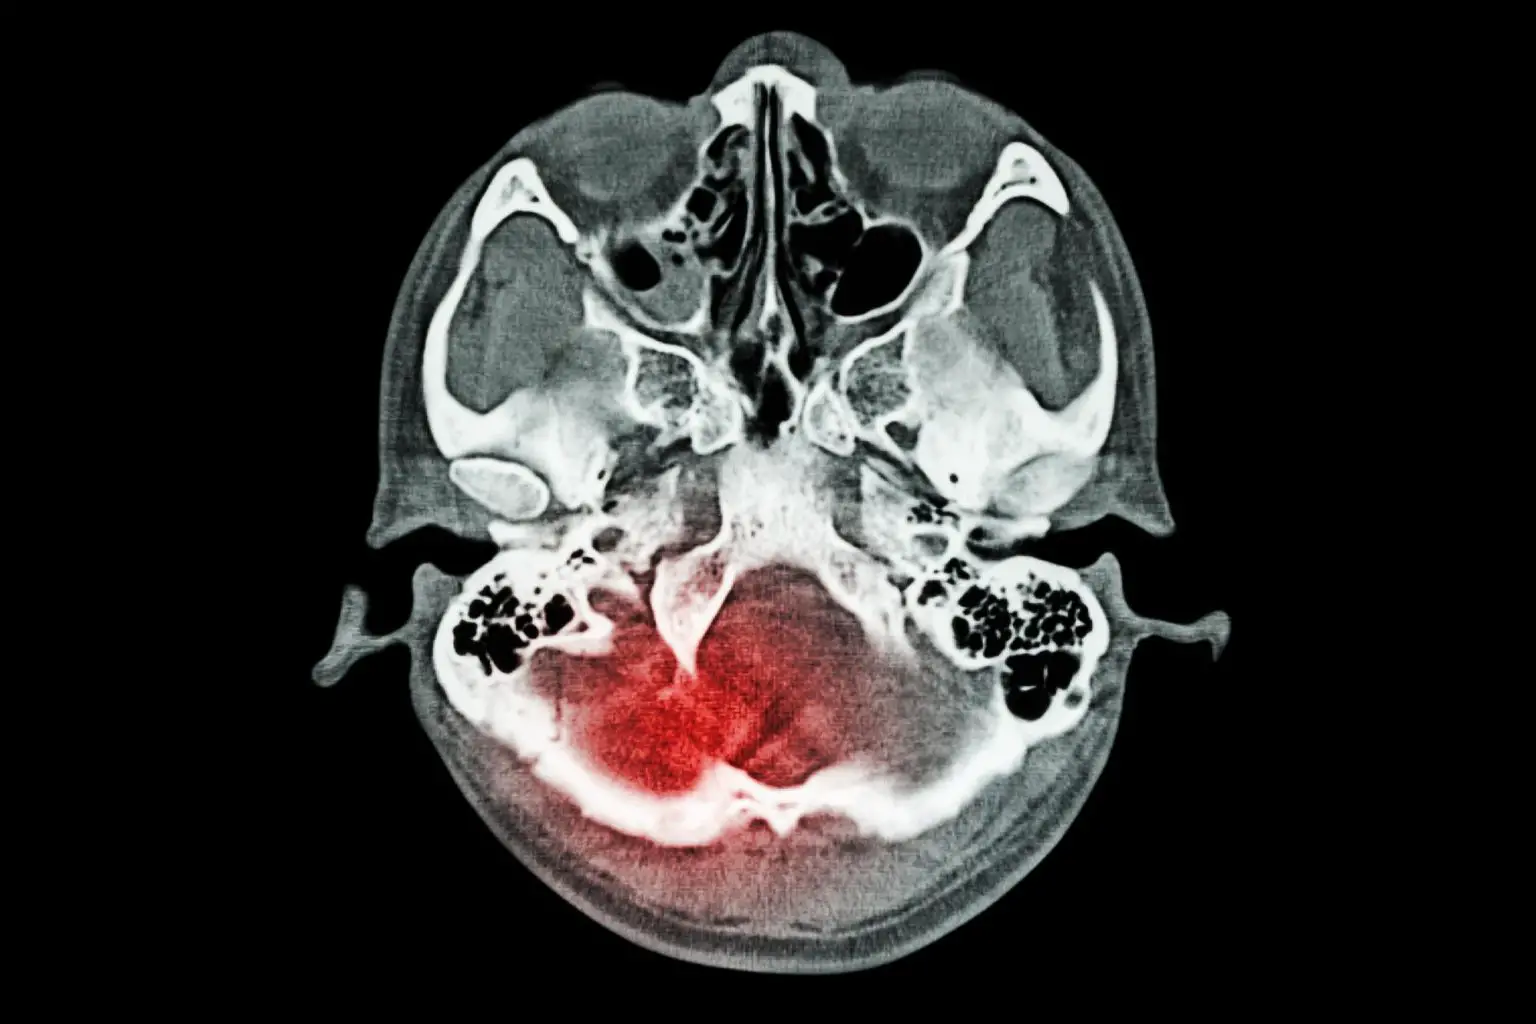

创伤性脑损伤(TBI)是一种由突然的外力或冲击造成的脑损伤,它扰乱了大脑的正常功能。它可以由跌倒、车祸、运动伤害或暴力等事件引起,其严重程度从轻微脑震荡到严重脑损伤不等。脑震荡可能导致暂时或永久的认知、身体和情感损伤,其症状包括头痛、记忆丧失、注意力难以集中、情绪波动,以及语言或运动功能的改变。治疗和恢复取决于伤害的严重程度,可能涉及医疗干预、康复和持续支持。

林斯曼说:"在年轻时得到的脑震荡会造成持续的潜在损害,其中一些损害可能是持续的神经炎症。例如,我们发现患有莱姆病的人有一定的神经系统症状,但如果他们有脑震荡的历史,这些症状会更严重。我认为这与COVID相似。这些都是神经营养性的,所以它们进入大脑。它们会引起炎症。如果它们在持续不断的神经炎症背景下这样做,比如头部受伤的历史,基本上就会对大脑产生累积效应。"